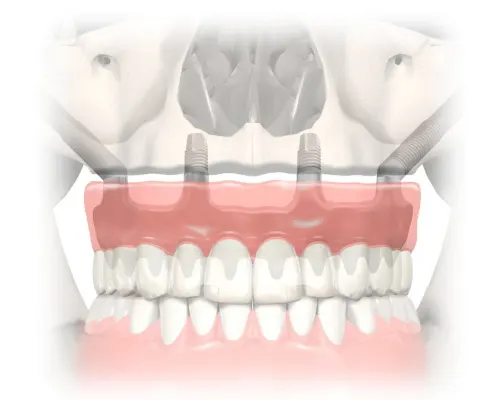

ทันตกรรมรากเทียมระบบ Zygoma เป็นทางเลือกในการทดแทนฟันที่สูญเสียไป โดยเฉพาะในกรณีของผู้ป่วยที่มีสภาพกระดูกรองรับฟันที่ไม่แข็งแรง สามารถหลีกเลี่ยงการปลูกกระดูกก่อนการปลูกรากเทียมได้

ด้วยเทคนิคการปลูกรากเทียม ระบบ zygoma ผู้ป่วยสามารถเข้ารับการถอนฟันและปลูกรากเทียมได้ในครั้งเดียวกัน หลังจากนั้นทันตแพทย์จะทำการติดยึดสะพานฟันอะครีลิกบนรากเทียมโดยประมาณ 1 ถึง 2 วันหลังการผ่าตัดปลูกรากเทียม

- รากเทียมระบบ zygoma สามารถใช้รักษาได้ในกรณีที่ผู้ป่วยมีปัญหาการสลายตัวของกระดูกรองรับฟันอย่างมาก

- รากเทียมระบบ zygoma สามารถทำได้โดยผู้ป่วยไม่ต้องเข้ารับการปลูกกระดูกเพื่อใช้รองรับรากเทียม

- รากเทียมระบบ zygomatic ใช้เวลาเพียงสั้นๆในการรักษา รวมทั้งผู้ป่วยสามารถใช้งานฟันได้ทันที

- ความเป็นไปได้ที่ผู้ป่วยจะได้รับการปลูกรากเทียมบนกระดูกบริเวณโหนกแก้มด้านในอย่างน้อย 2 ตำแหน่ง